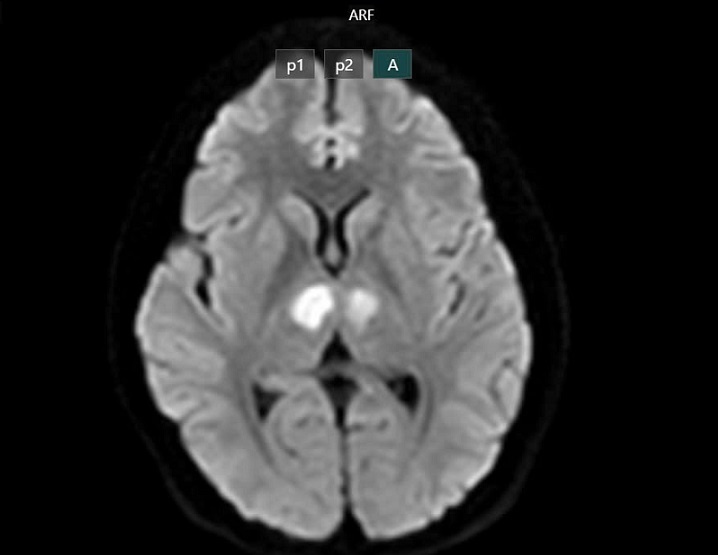

Kết quả chụp MRI cho thấy bệnh nhân bị tổn thương vùng đồi thị hai bên. Kết quả kiểm nghiệm mẫu thuốc cho thấy có chứa Sibutramin, một chất đã bị cấm lưu hành tại Việt Nam từ năm 2011 do nguy cơ gây đột quỵ, rối loạn tim mạch và tử vong.

Phim chụp cho thấy não bệnh nhân bị tổn thương vùng đồi thị hai bên. (Ảnh: BV Bạch Mai)